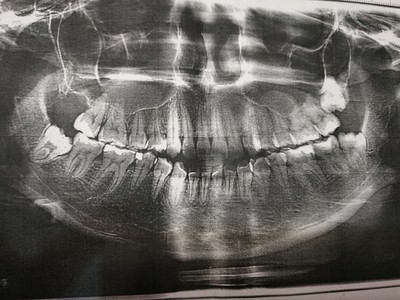

Посмотрите на снимки. Между верхним и нижним — разница в три недели. По ним хорошо заметно, что после удаления зачатков восьмёрок и «разблокировки», седьмые зубы сразу пошли в рост.